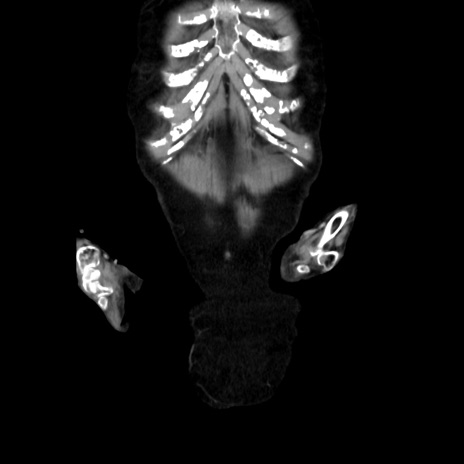

症例40(冠状断像)

【症例】90歳代女性

【主訴】腹痛・嘔吐

【現病歴】 食欲低下、嘔吐があり昨日他院受診。肺炎と診断され入院となる。入院後より腹部全体に圧痛あり。胃管留置され経過みていたが、症状持続するため、

当院転院となる。

【身体所見】腹部:中央に激痛あり、圧痛あり、反跳痛不明

【データ】WBC 17100、CRP 18.82

冠状断像